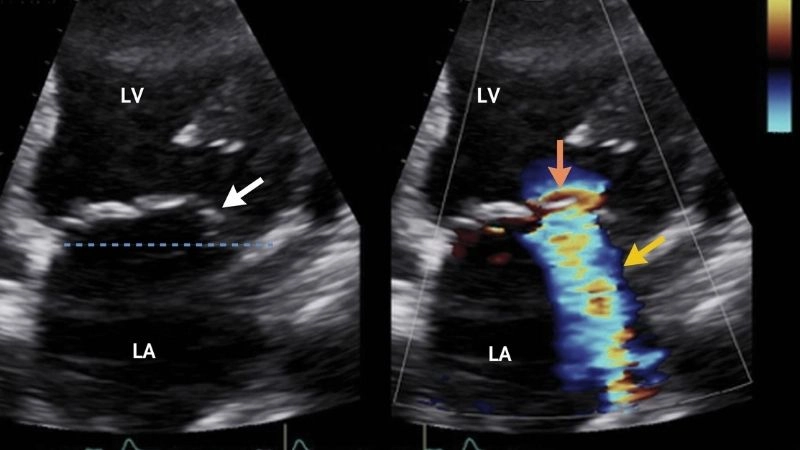

Images visual examples of mitral regurgitation (Insufficiency)

Mitral regurgitation occurs when the mitral valve does not close properly, allowing blood to leak backward into the left atrium and overloading the heart.